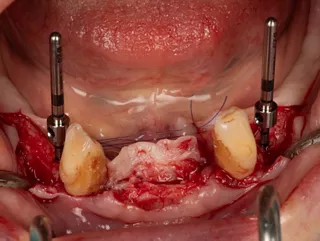

3a. Elevation of the full-thickness flap by crestal incision centred on the keratinised and sulcular tissues in 33 and 43.

The canines are preserved to provide an indication of the drilling axis.

Initial drilling in 32 and 42 using the first 1.5 mm drill bit, then positioning of directional indicators to assist with subsequent drilling. Drilling to 12 mm is checked using the graduation on the initial drill bit.

3a

3b

3b. Drilling adjacent to the remaining teeth 33 and 43 using the initial 1.5 mm drill. Depth and axis checked using the anterior indicators and residual canines.

Given the average bone density (D2 to D3), only the initial drill was used to the working length of 12 mm.